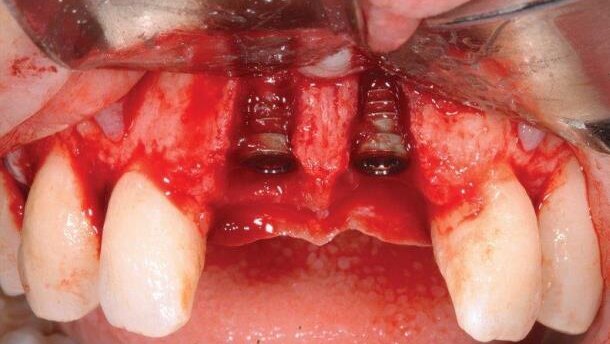

Wykonano osteotomie i wszczepiono 2 implanty 3i T3® Tapered (oba o średnicy 4 mm x 3.4 mm platform i długości 13 mm).

Autor prezentuje przypadek ekstrakcji z wczesną implantacją i jednoczasowym przeszczepem kości i tkanek miękkich.

29-letnia pacjentka zgłosiła się z bólem siekaczy centralnych. Na zdjęciu radiologicznym zauważono zmiany okołowierzchołkowe. Plan leczenia zakładał ekstrakcję zębów z 5-tygodniowym okresem gojenia tkanek miękkich, implantację wczesną z jednoczasowym przeszczepem kości i tkanek miękkich oraz okres gojenia pozwalający na remodeling dziąsła. Po uzyskaniu zgody pacjenta, leczenie przebiegało następująco: